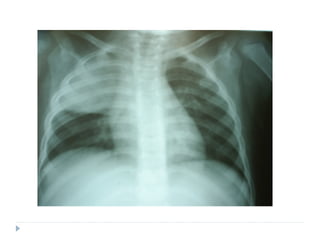

Radiografia

 Não precisa ser feita na criança tratada em casa.

 Radiografias em perfil não precisam ser feitas rotineiramente,

em todos os casos.

 A imagem radiológica não distingue etiologia viral ou

bacteriana.

 Não se recomenda radiografias de controle, exceto para

pneumonias complicadas, como com derrame pleural ou

atelectasia.

Manifestações radiográficas